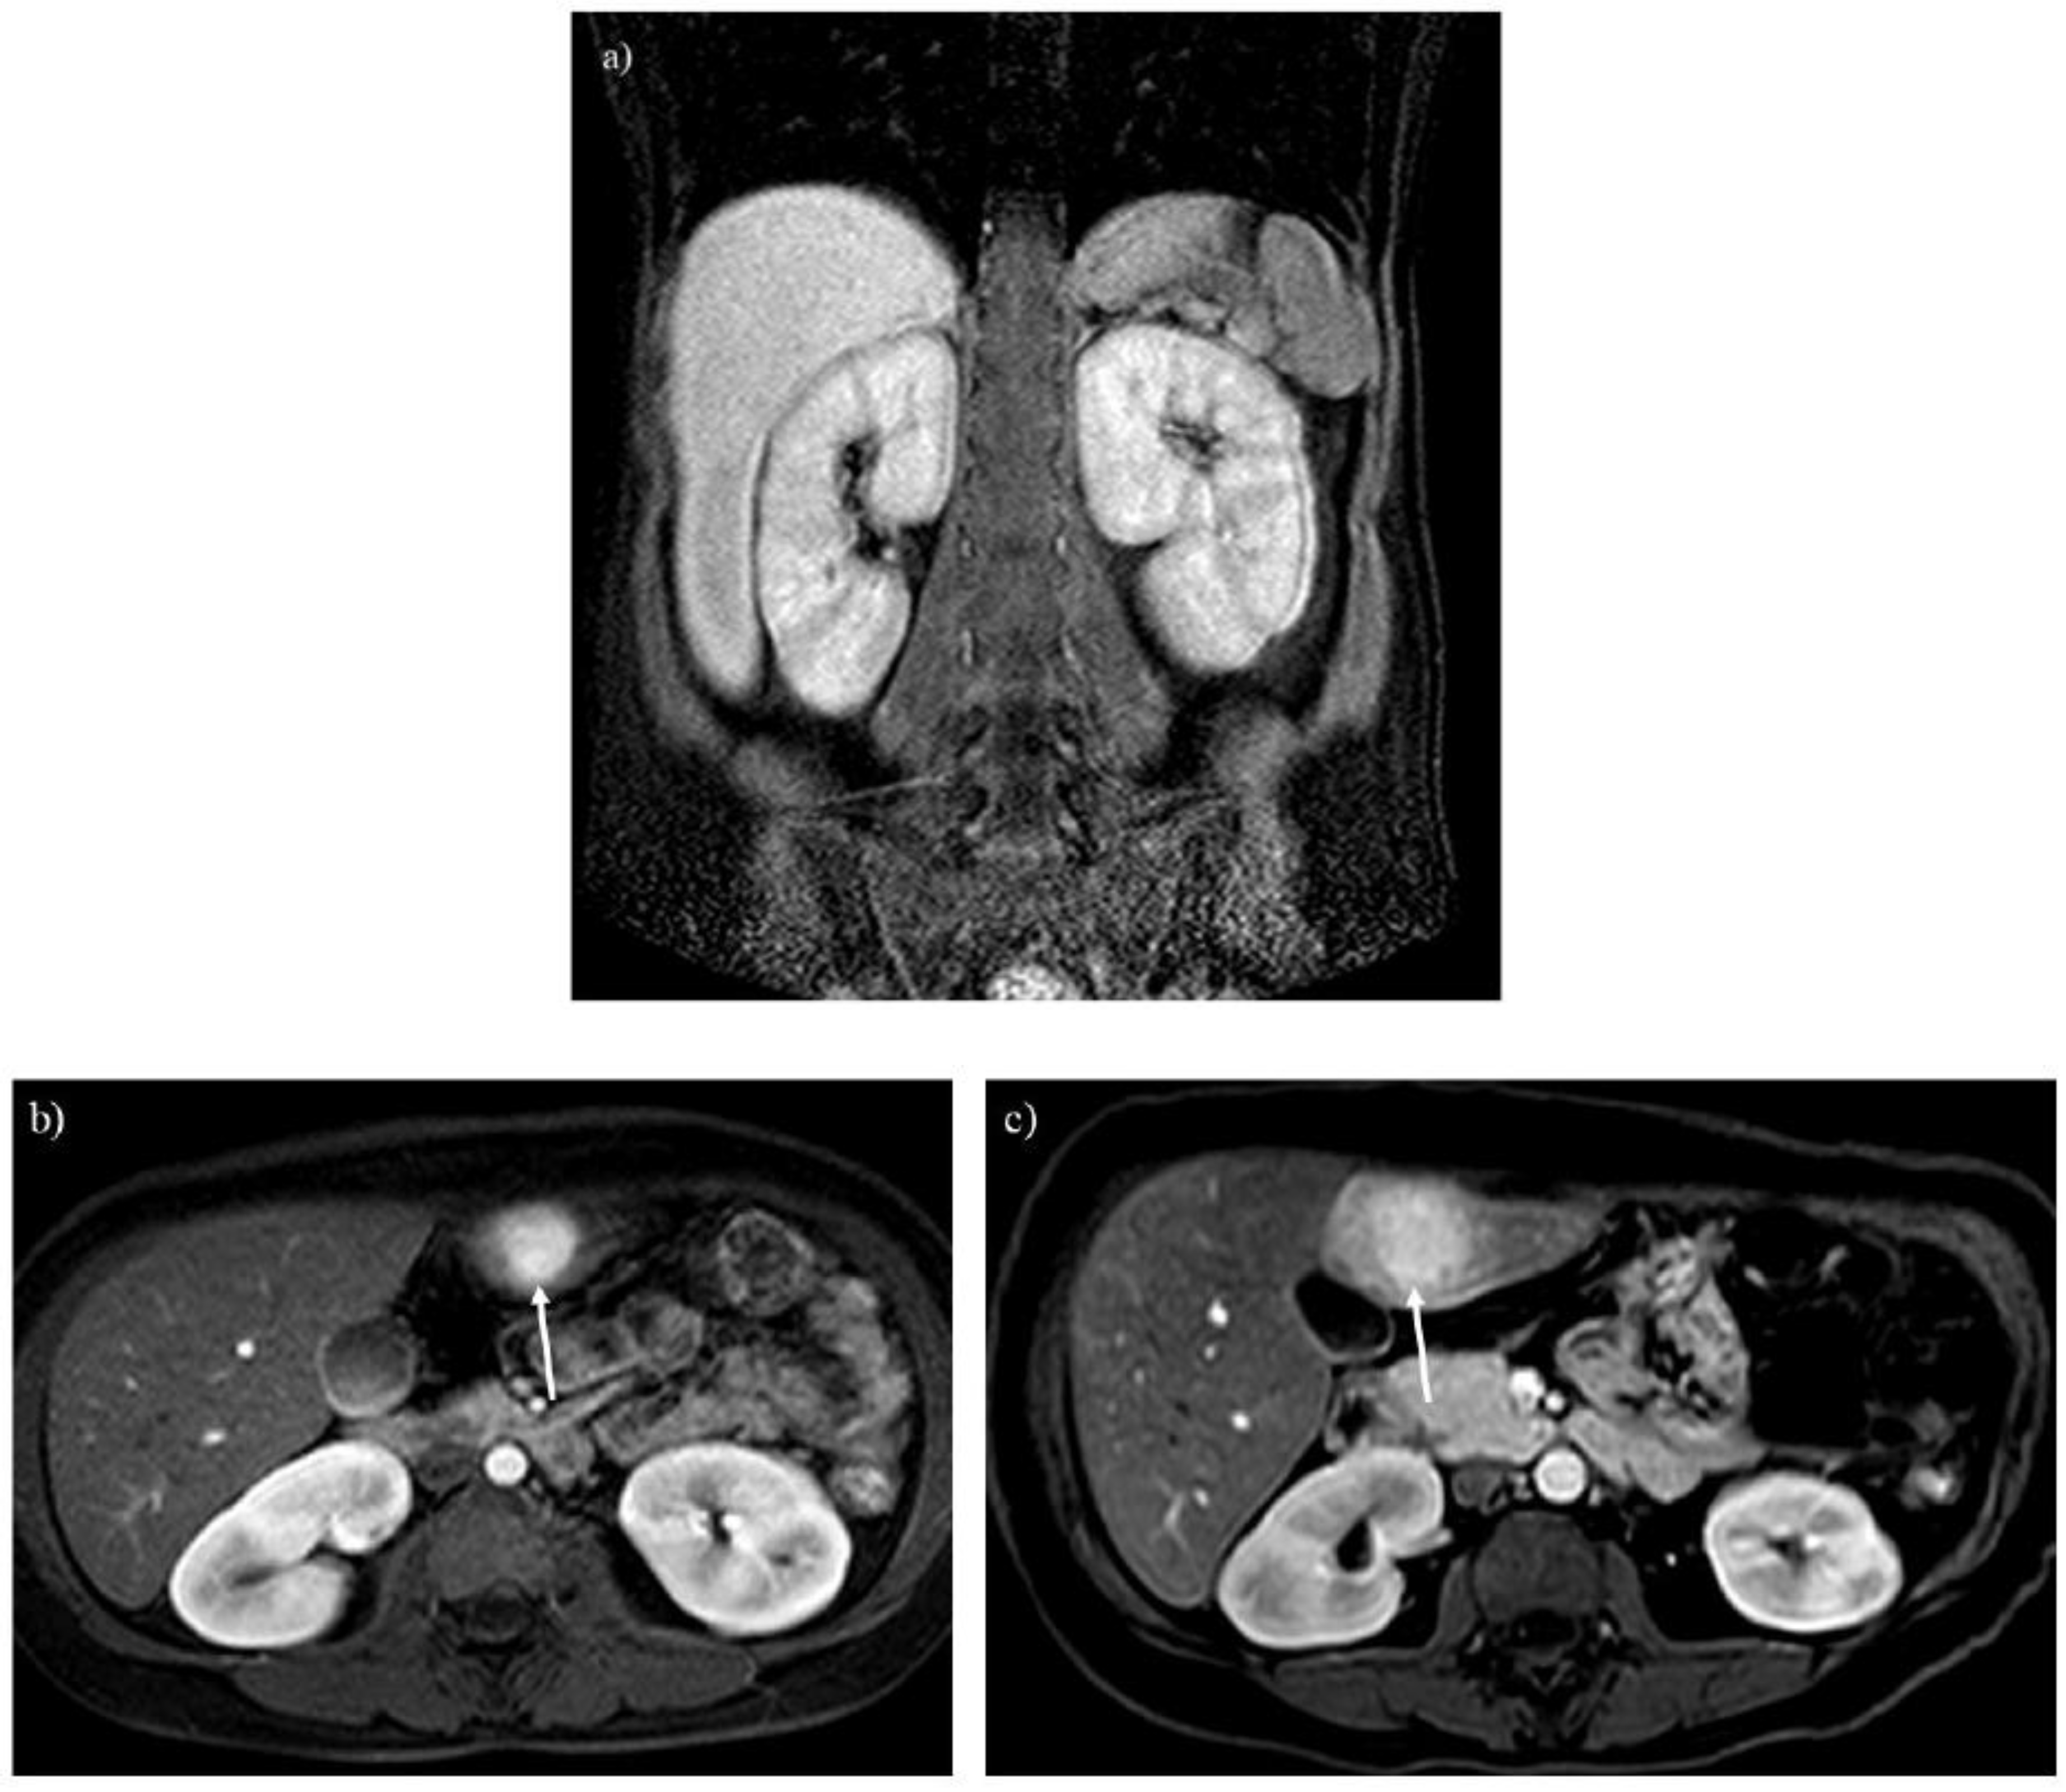

Glycogen and similar materials accumulate in the kidneys, which induces renal complications in patients with GSDs [1,2,3,5,14]. MRI is insensitive to renal calculi associated with GSDs, whereas it can detect enlargement or atrophy of the kidneys (Figures 2A and 3A). T1-weighted imaging identifies renal impairment as decreased corticomedullary contrast in the kidneys (Figure 2A) [15]. MRI can also be used to investigate transplanted kidneys without contrast agents (Figure 2B).

Figure 2. Renal atrophy is observed on T1-weighted imaging in a 40-year-old woman with glycogen storage disease type Ia. The atrophic kidneys lose corticomedullary contrast on T1-weighted imaging (A). A transplanted kidney shows normal corticomedullary contrast on T1-weighted imaging (B).

Figure 3. A 20-year-old woman with glycogen storage disease type Ia exhibiting enlargement of the kidney (A). Dynamic MRI (B) reveals a hepatic adenoma presenting strong enhancement in the arterial phase (arrow), and the tumor gradually enlarged over 13 years (C, arrow).